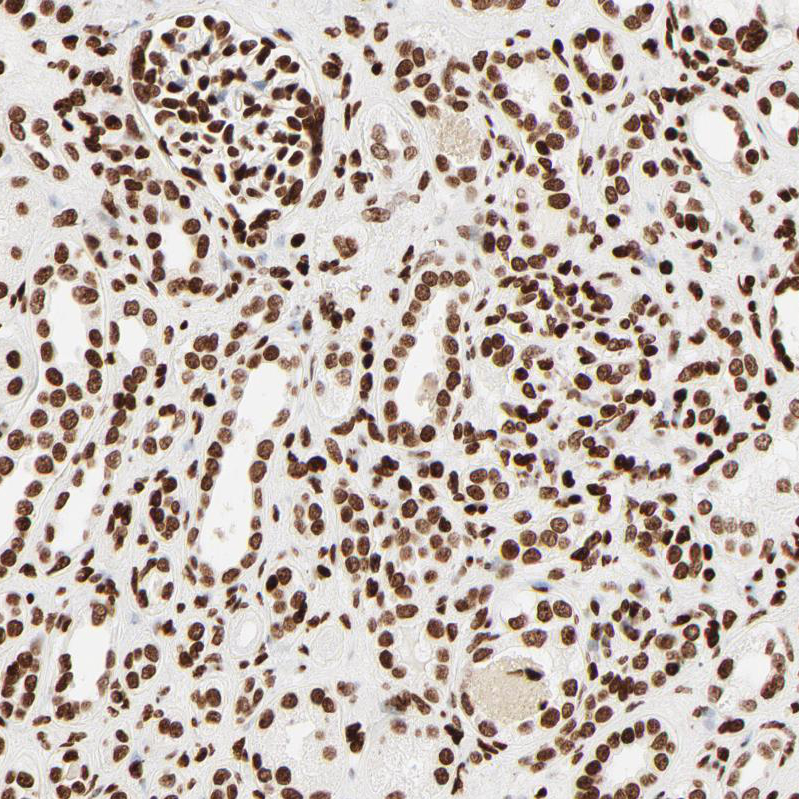

Immunohistochemical staining of human bone marrow shows strong nuclear positivity in hematopoietic cells.